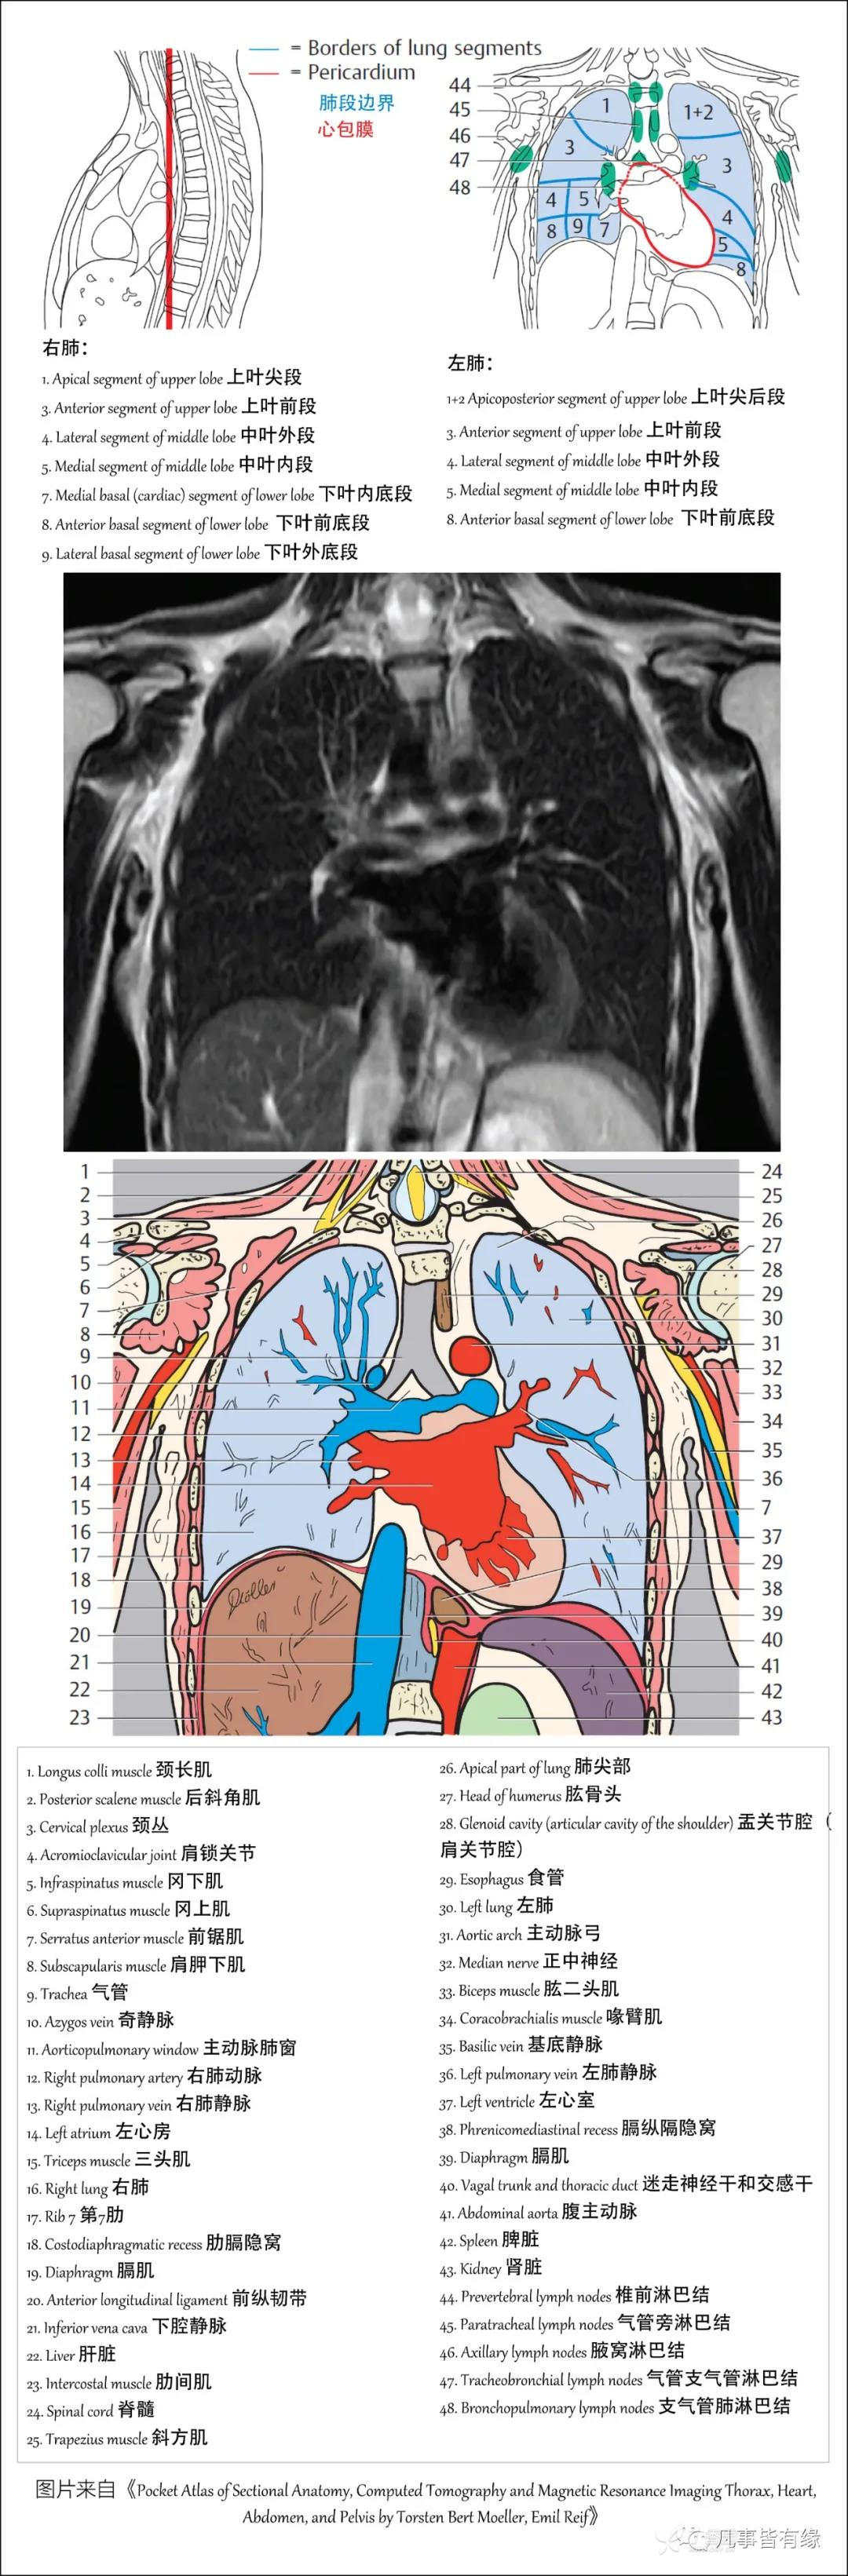

(一)胸部CT轴位断层解剖: